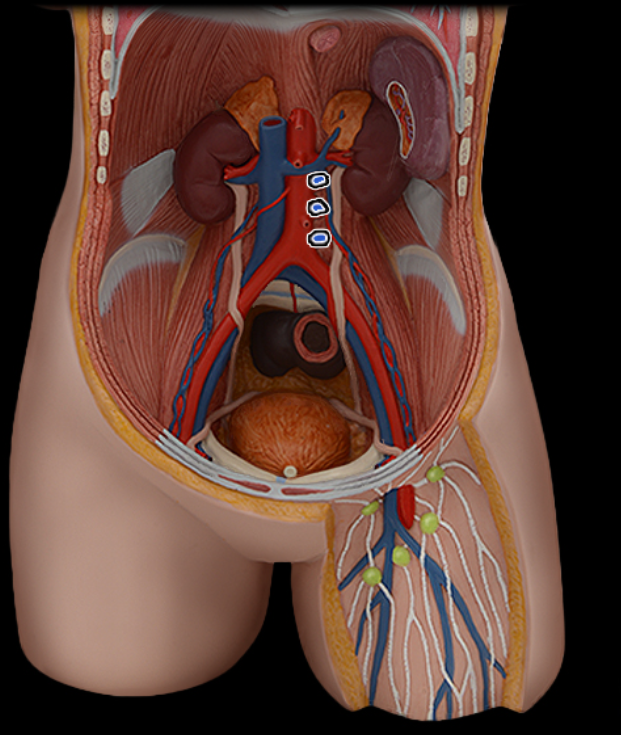

Abdominal aorta

Common iliac a.

Common iliac v.

External iliac a.

External iliac v.

Femoral a.

Femoral v.

Gonadal a.

Gonadal v.

Inferior vena cava

Lumbar a.

Lumbar v.

Renal a.

Renal v.

Superior mesenteric a.